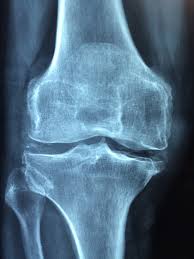

콘드로이친은 연골을 구성하는 중요한 성분 중 하나입니다. 사람의 관절에는 연골이 존재하는데 이 연골은 충격을 흡수하고 뼈와 뼈 사이의 마찰을 줄여주는 역할을 합니다. 콘드로이친은 이러한 연골을 보호하고 유지하는 데 도움을 줄 수 있는 성분으로 알려져 있습니다.

나이가 들수록 연골은 점점 닳게 되는데 이때 콘드로이친 섭취가 도움이 될 수 있습니다. 실제로 관절 건강 영양제에 콘드로이친이 많이 포함되는 이유도 연골 보호 기능 때문입니다.

콘드로이친 효능 중 가장 대표적인 것은 관절 건강 개선입니다. 연골 조직을 구성하는 성분이기 때문에 관절 마모를 줄이고 움직임을 부드럽게 하는 데 도움을 줄 수 있습니다.

특히 무릎 관절이나 손가락 관절처럼 반복적으로 사용되는 부위에서 통증 완화에 도움을 줄 수 있다는 연구도 있습니다. 관절염 초기 단계에서 보조적으로 활용되는 경우도 많습니다.

콘드로이친은 연골 내부에서 수분을 유지하는 역할을 합니다. 연골이 충분한 수분을 유지해야 탄력이 유지되고 관절 충격을 잘 흡수할 수 있습니다.

또한 연골 분해 효소의 활동을 억제하는 작용이 보고되면서 연골 손상 속도를 늦추는 데 도움을 줄 수 있다는 연구도 있습니다. 그래서 중년 이후 관절 건강 관리 영양제로 많이 사용됩니다.